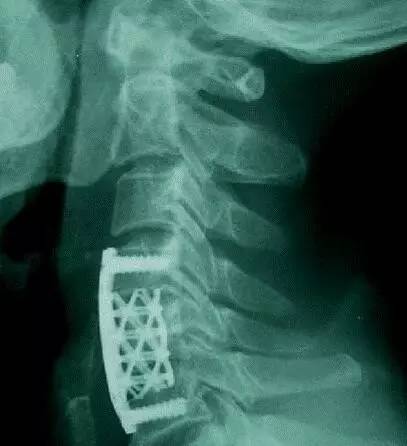

用来替换4节颈椎的3D打印内植物(是不是跟想象中的完全不一样,做成这样是有原因的,后文会告诉你)。该内植物通过两端的接头直接固定在第一节和第六节椎骨上。它的力学强度和与上下椎骨的接触面积,都明显大于传统的钛网。一段时间后,这个具备人体生理曲度的「海绵状」微孔钛合金3D打印内植物会被新生的骨组织充满(见下图),并被各种软组织包被。(北医三院供图)

在技术相对成熟的今天,定制3D打印内植物的过程并不复杂。首先给病人做CT扫描获取患者的颈椎数据,并用专业的软件把CT扫描的数据转换成3D打印的数据,然后就可以打印出患者的颈椎模型。医务人员再根据这个颈椎模型来设计内植物的大小,曲度和形态,然后把数据输入到相关的设备里面,只需开动机器打印就行了。按照目前的设备,打印这个替代4节椎骨的内植物大概需要13个小时左右。

奇点一直以为定制化3D打印椎骨跟人体的椎骨一模一样,然而并不是,而且完全不一样。后来奇点了解到,定制化3D打印椎骨之所以跟椎骨不一样,主要是考虑到实用性。因为颈椎中布满神经、血管和脊髓,所以为了便于手术中操作方便,在满足力学强度的前提下,就要把植入物设计的相对小一些。这样对患者的创伤也较小,更有利于患者快速恢复。

这个定制化3D打印椎骨最大的难点和亮点是通体「海绵状」的微孔结构。这就意味着整个内植物都是由微孔组成的。这样设计的目的主要是为了让人的骨头可以直接长到微孔里面,和这个内植物实现融合(7)。这也是跟钛网最主要的区别。